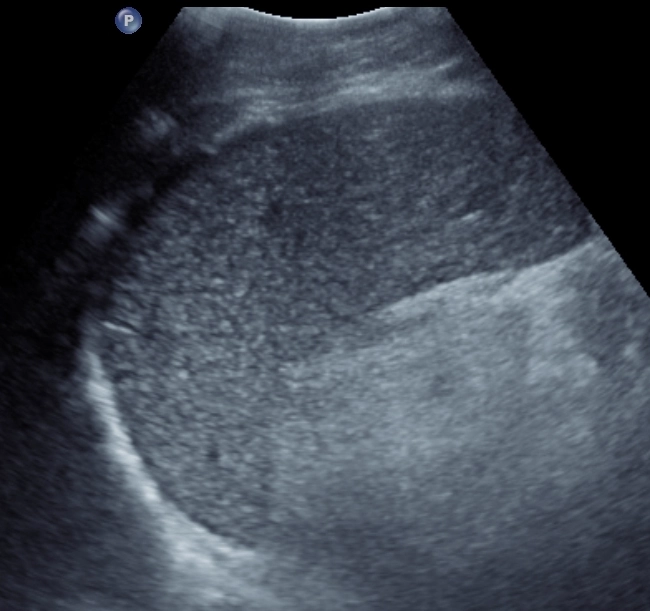

• Lách to (Splenomegaly)